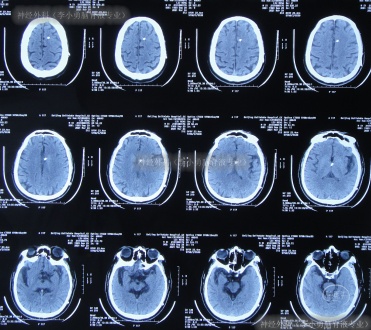

但出院后1个月即2020年12月6日(脑室腹腔分流术后3年零2月),再次出现嗜睡,第3次就诊该院,查头颅CT(片子丢失)后认为脑室系统与1月前相比并未明显扩张,但第2天即2020年12月7日,出现昏迷,大小便失禁,再查头颅CT(图-3)后认为脑室有大。

图-3:2020年12月7日头颅CT